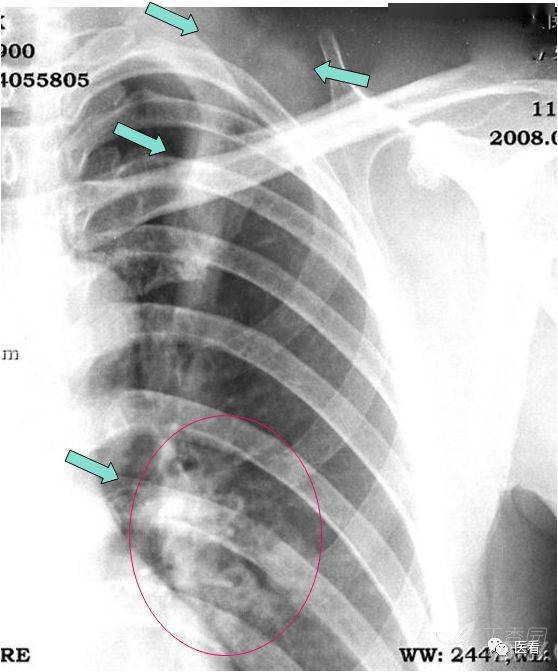

胸部 粗看x光片,细看ct

下列胸部平片和ct片(不同病人)是什么疾病?